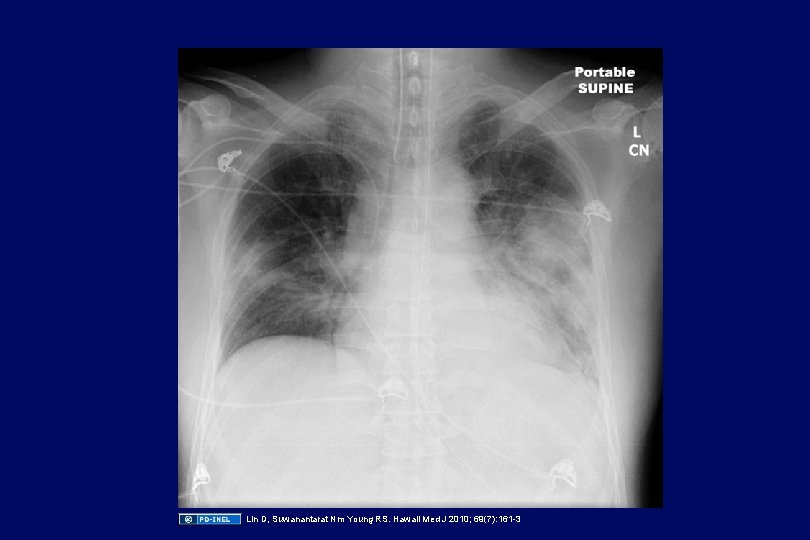

Case: neck and chest pain • A 22 year old male who recently had an prolonged episode of pharyngitis now presents with high fever, and exquisite pain, tenderness and swelling of his left neck for 2 days. • This morning, he developed sharp pain in the left lower chest with deep breathing • A blood culture is positive for an anaerobe

Lin D, Suwanantarat Nm Young RS. Hawaii Med J 2010; 69(7): 161 -3

Lin D, Suwanantarat Nm Young RS. Hawaii Med J 2010; 69(7): 161 -3

Lemierre’s syndrome • Or “post-anginal sepsis” (very rare) • Occurs after prolonged or severe pharyngitis • Septic thrombophlebitis with Fusobacterium necrophorum (probably from the mouth) associated with septic pulmonary emboli to the lungs